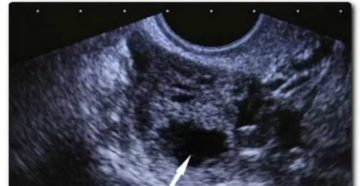

Причины неразвивающейся беременности пятница, мая 20, 2016 — 13:55 Плодным яйцом называется структура, окружающая эмбрион…